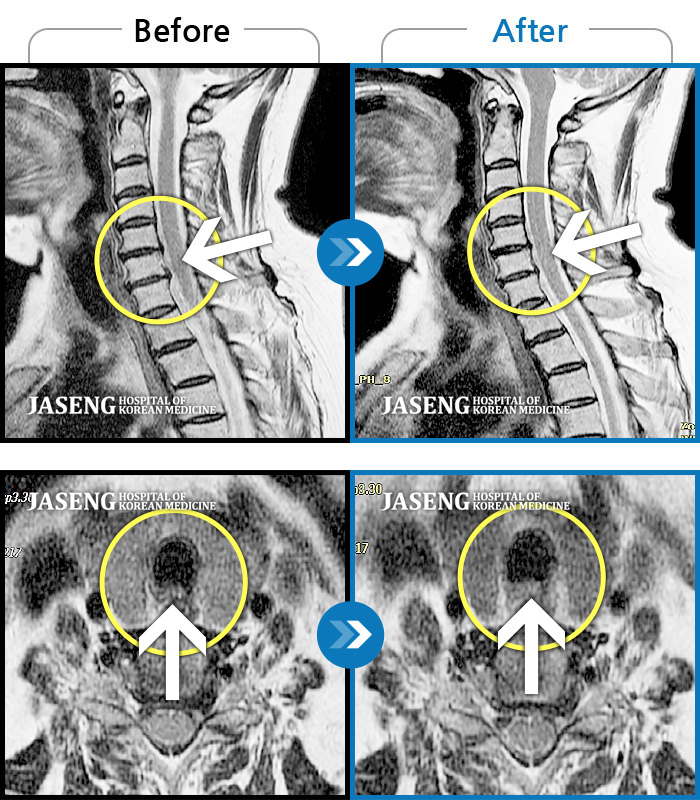

목디스크

도움받은 사례

인천 · 강아현 원장

처음 내원시 목에서 등으로 이어지는 통증 및 우측 팔 저림 증상이 심했고, 약간의 근력저하도 동반되어 일상생활이 어려운 상태였습니다.

촬영시기

2024.04.06 ~ 2024.11.16

2024.11.22

조회수 17,047